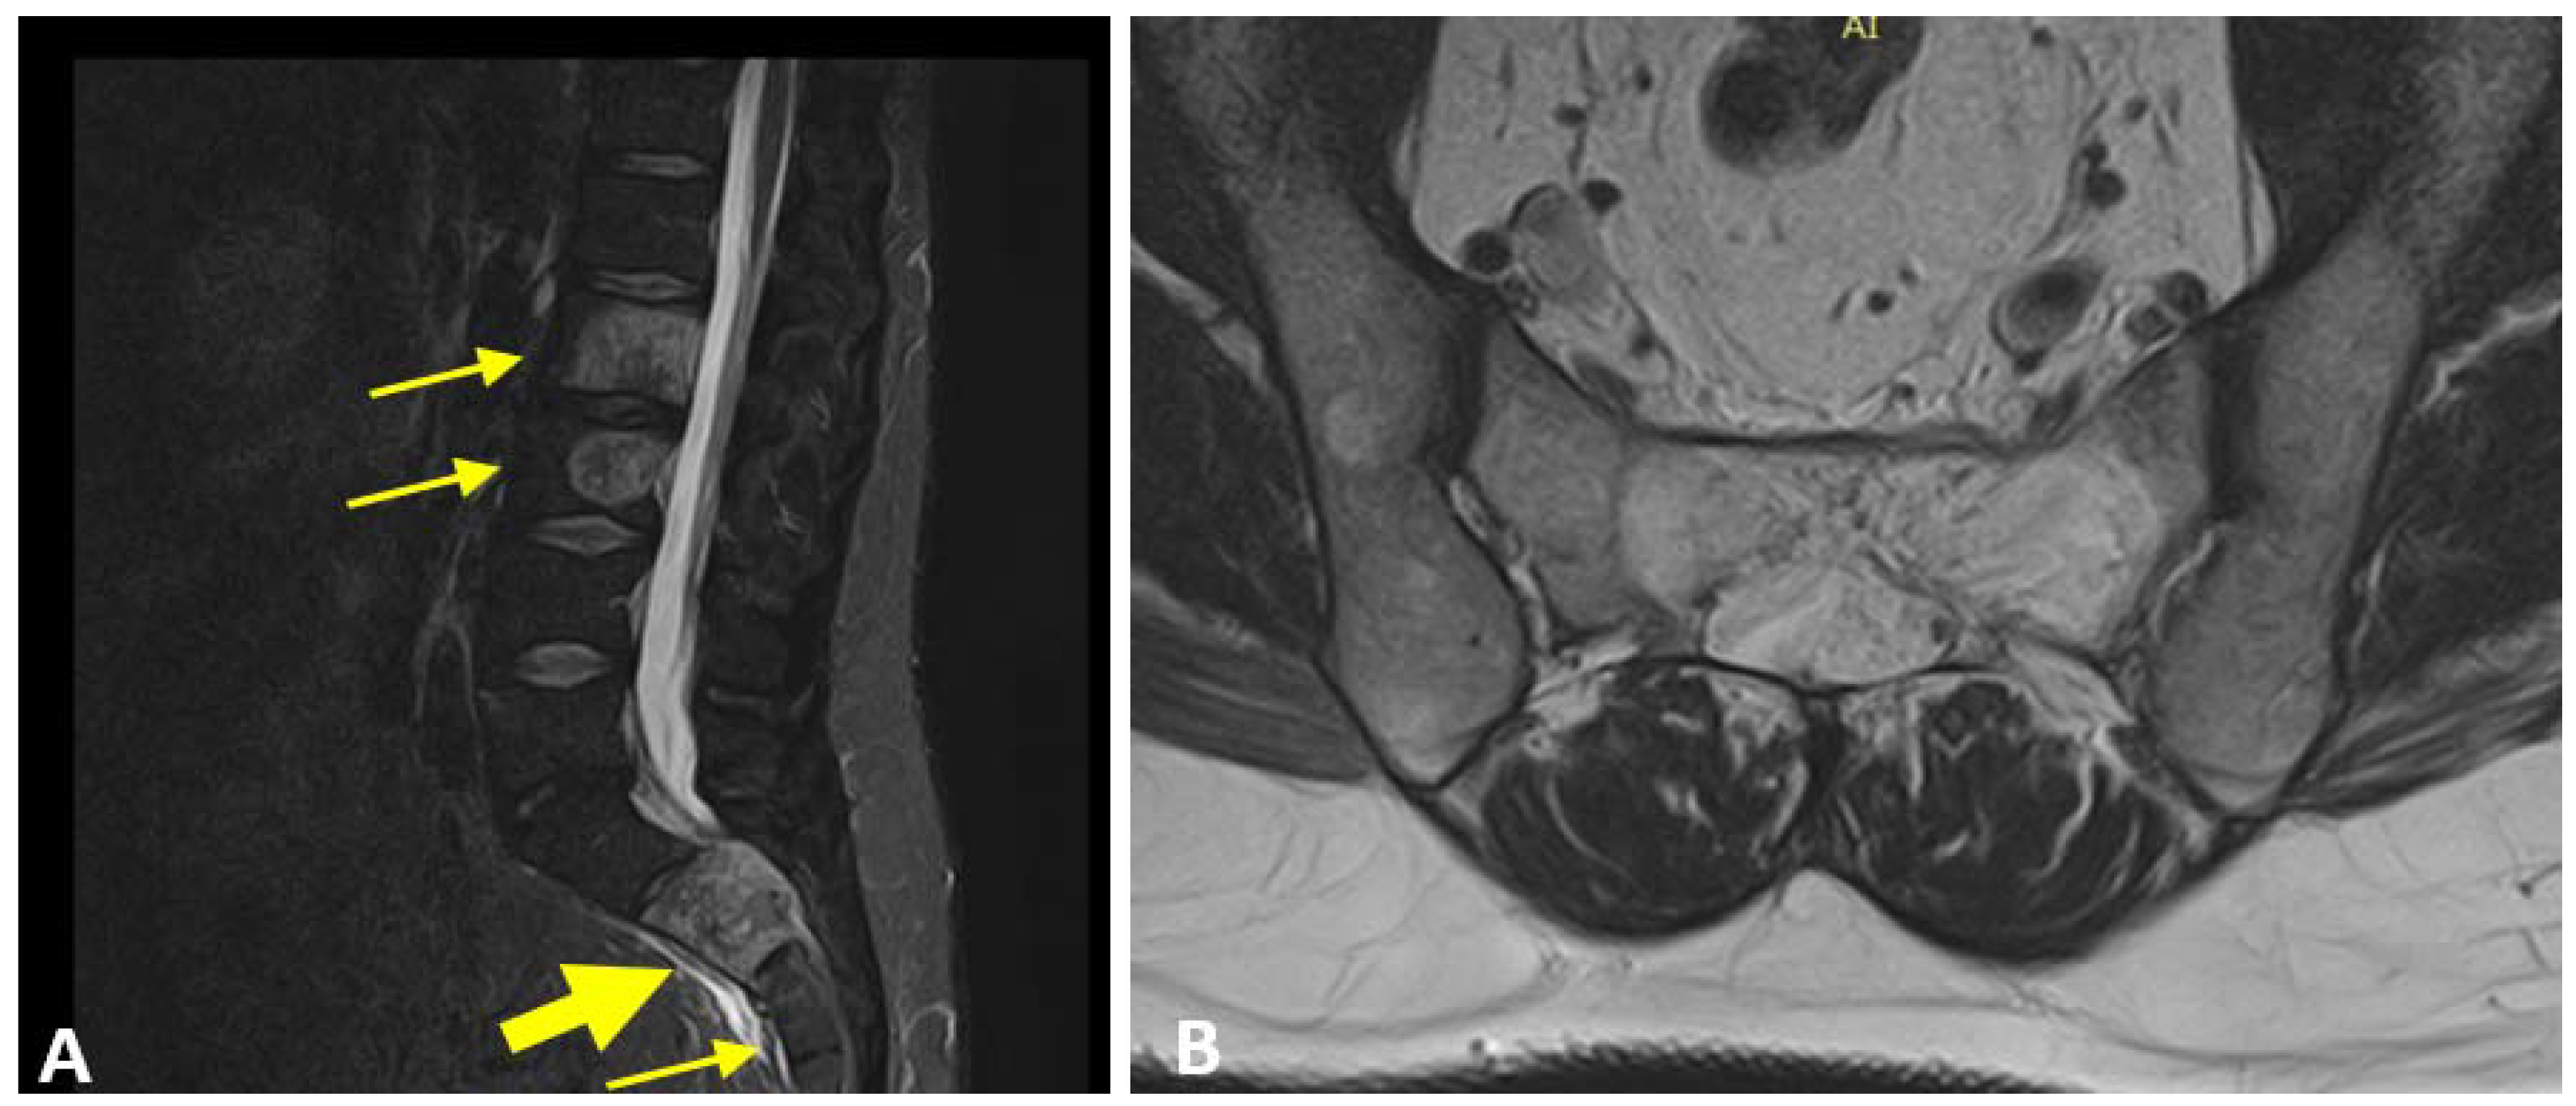

The neurosurgeon examined the patient and prescribed an MRI, which revealed: “lumbar and sacral multiple HAs characterized by T2 hyperintensity, revealing major vascular component. Numerous HAs limited into the vertebral bone in L1, L4, L5 and S3 and not occupying the pedicles area. Wide HAs extended into the left vertebral pedicles in L2 and L3, without overcoming the border of the vertebral cortex. Presence of large HAs which occupy the entire body of S2, exceed the posterior cortex and occupy the medullary space” (Figure 3A,B).

Figure 3. Multiple HAs were displayed in the lumbar and sacral vertebrae (little yellow arrows). S2 vertebral body (big yellow arrow) showed a wide HAs overcoming the cortex and occupying the medullary space ((A), sagittal view; (B), transversal view).